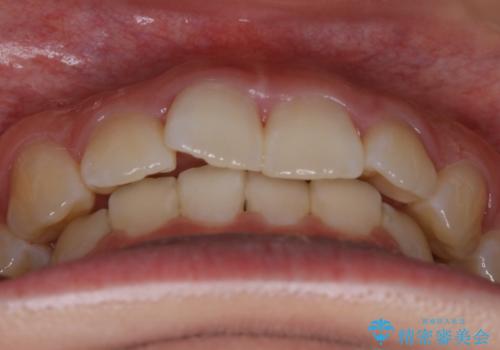

- 初診時、前歯のガタつきを主訴にご来院されました。

精密検査の結果奥歯の噛み合わせのズレからくる前歯のガタつきであることが分かり、患者様と相談した結果、全体をしっかりと治療することをご選択なさったので奥歯から動かして噛み合わせと見た目の両方を治す治療プランとなりました。

初診時の写真では一見噛み合わせには問題がないように見えても、実際に精密な検査を行うと改善すべき点が見つかる場合も多くあります。